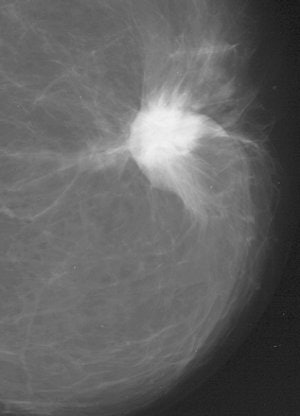

| False-negative case for all reviewers: 76-year-old woman with invasive ductal carcinoma. Above, craniocaudal mammogram obtained four years before study in which mass (arrow) was excised and was found to be benign (fibrocystic changes without atypia) at histology. Middle, screening mammogram, craniocaudal view, two years before study shows postsurgical changes. Below, screening mammogram, craniocaudal view, at time of study in which increase in density at biopsy site was not detected by any of reviewers, although area was marked by CAD system. |